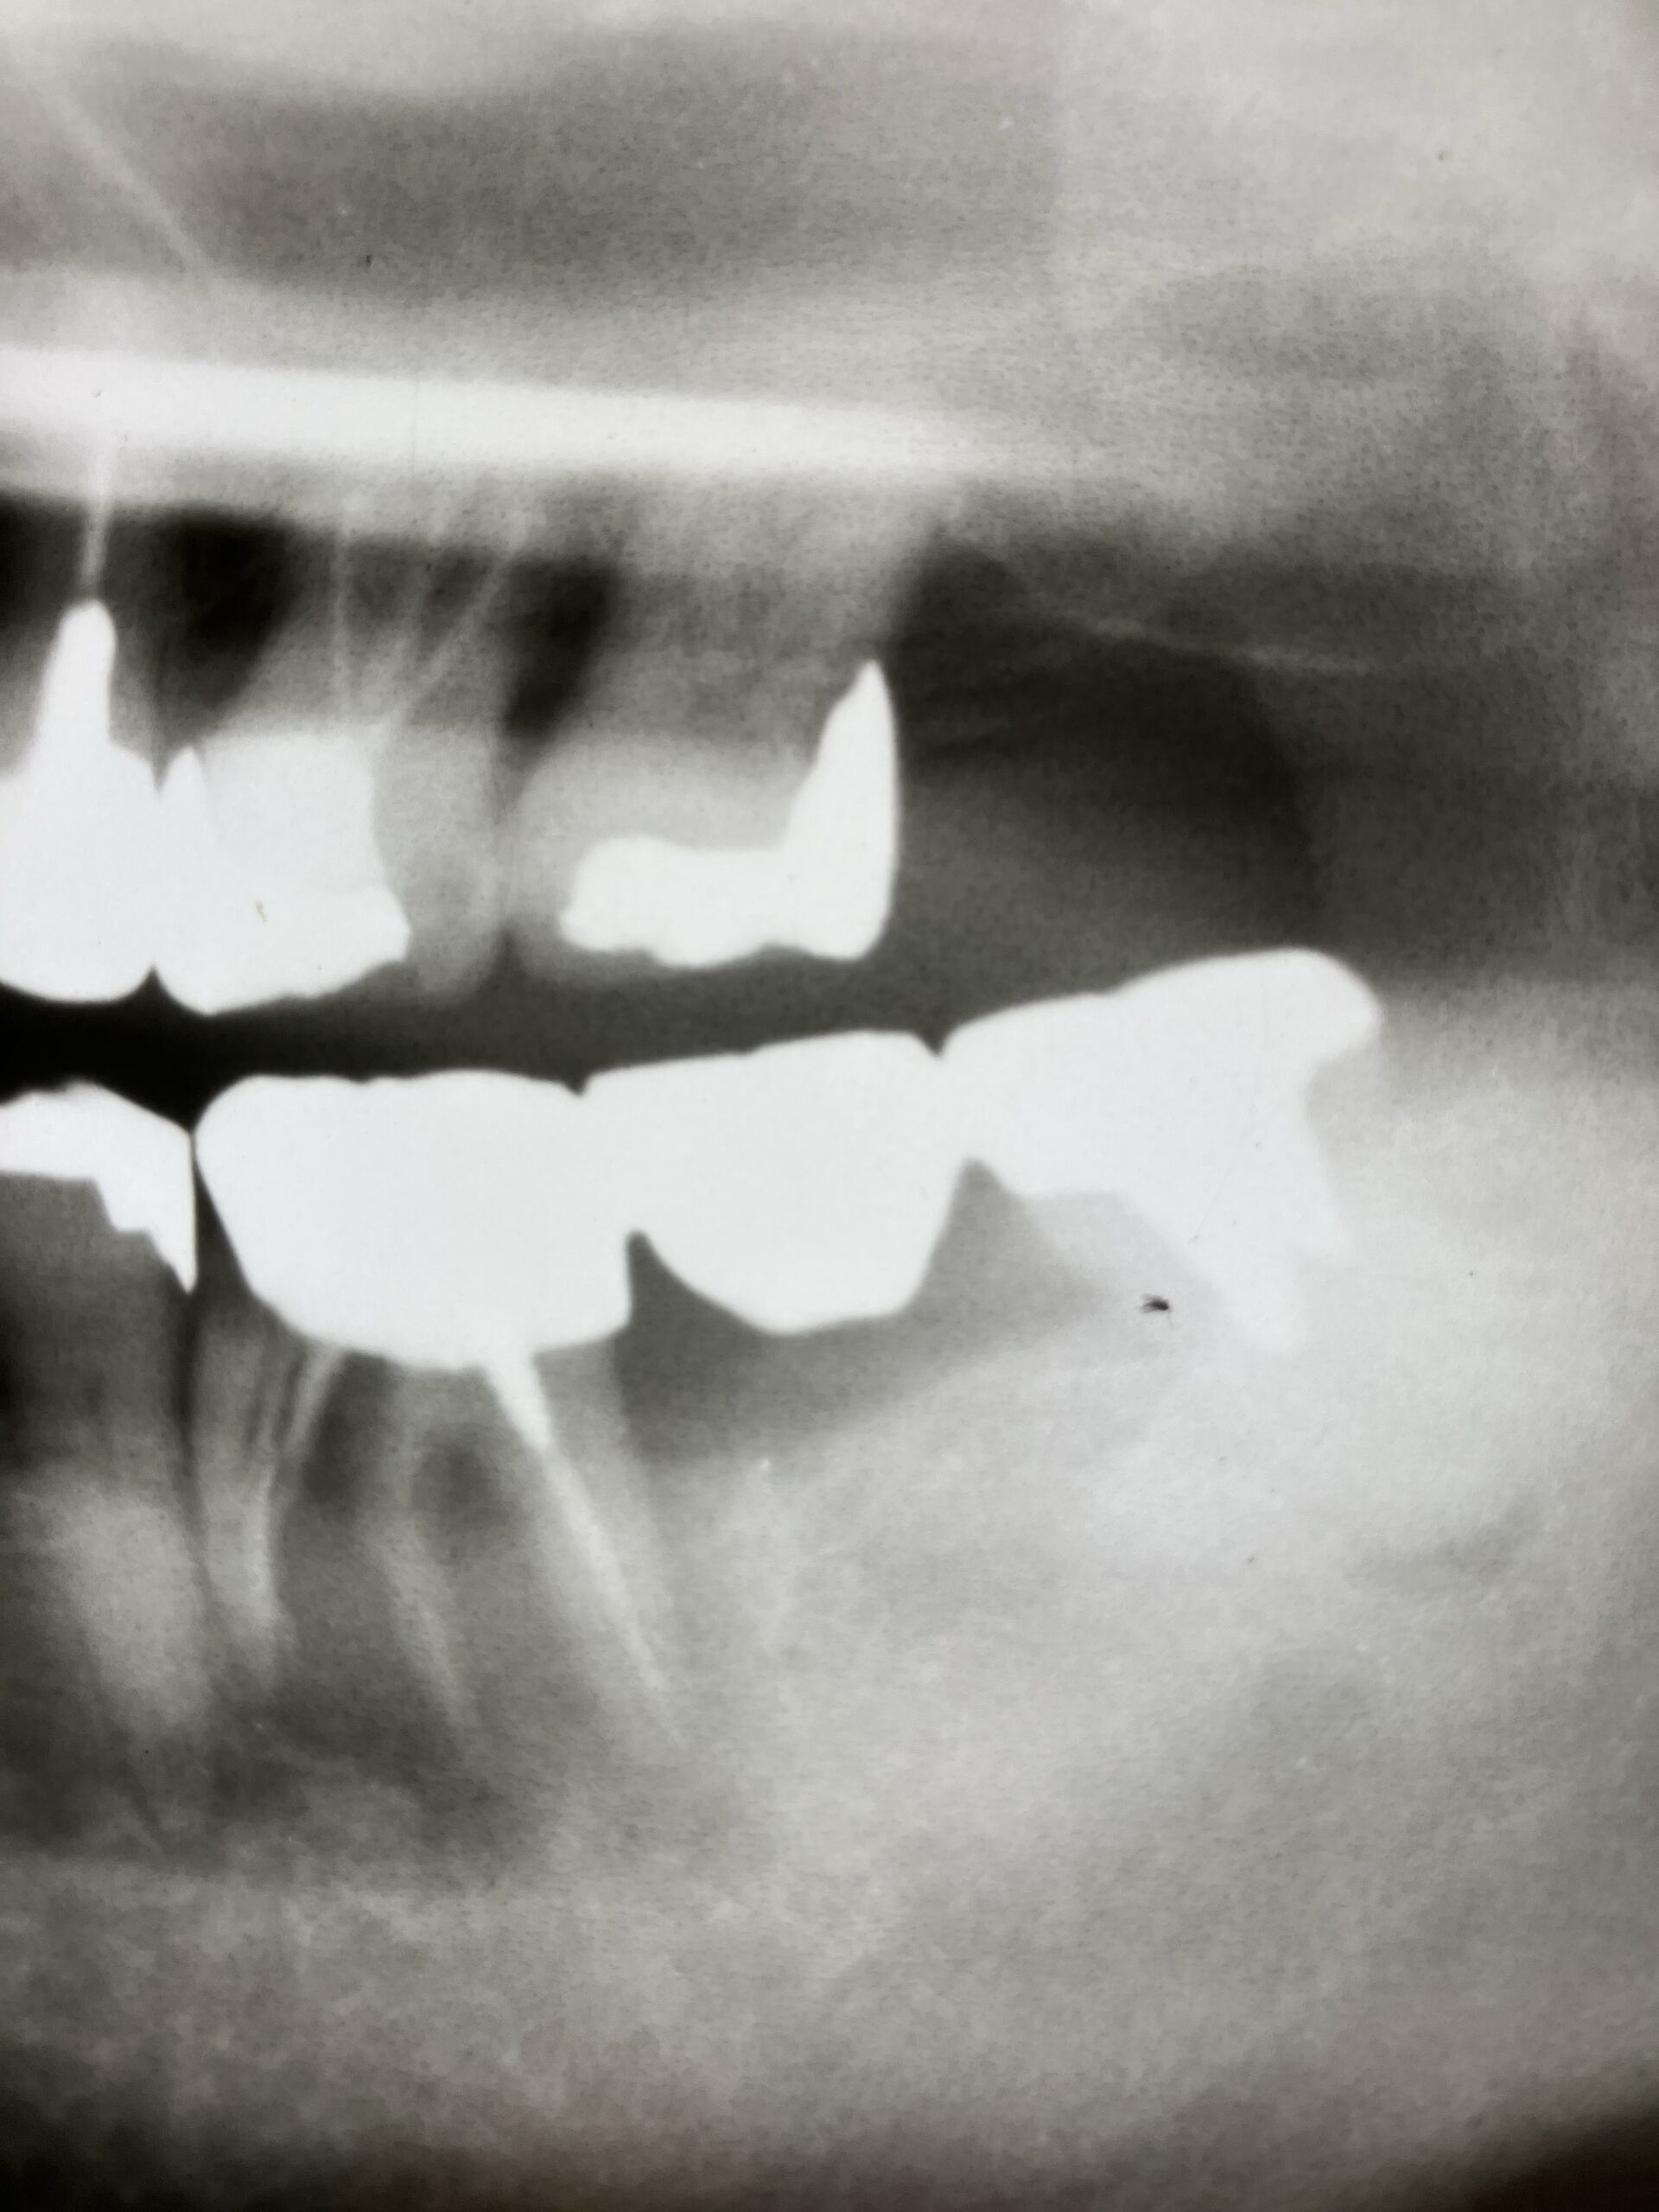

• レントゲン検査(X線検査): 歯根のひび割れや骨の状態を確認します。ただし、初期の細いひび割れはレントゲンに映らないこともあります。